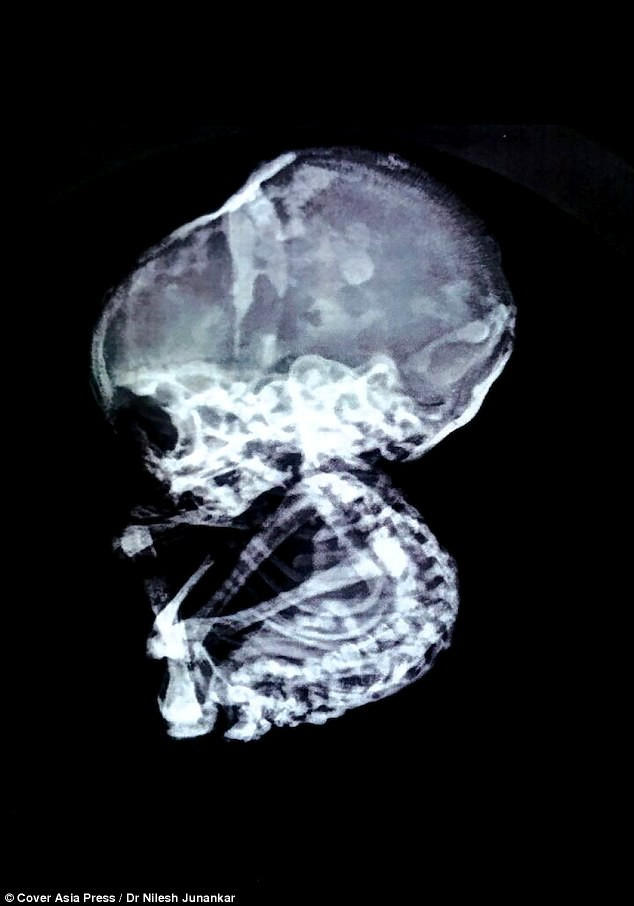

BS. Nilesh Junankar, người thực hiện ca phẫu thuật, cho biết chụp CAT cho thấy có một khối gây tắc nghẽn ruột và có cấu trúc như một khối đá.

Tiếp tục thực hiện nội soi, các bác sĩ của TT phẫu thuật Junankar (Nagpur) đã vô cùng sốc khi phát hiện khối đá gây tắc ruột đó là một thai nhi 4 tháng tuổi.

Bào thai đá vô cùng hiếm gặp với chỉ 300 ca được ghi nhận trên toàn thế giới trong 400 năm qua.